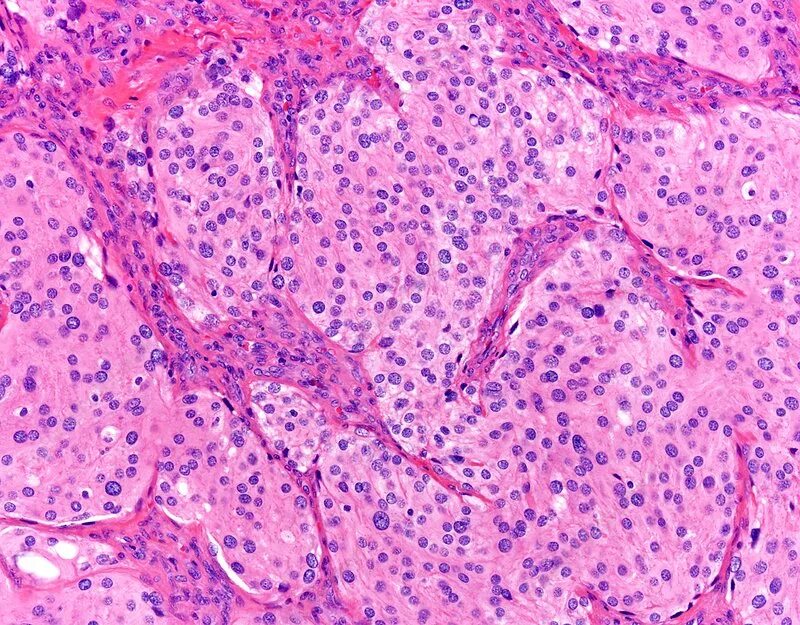

Молекулярная гистология